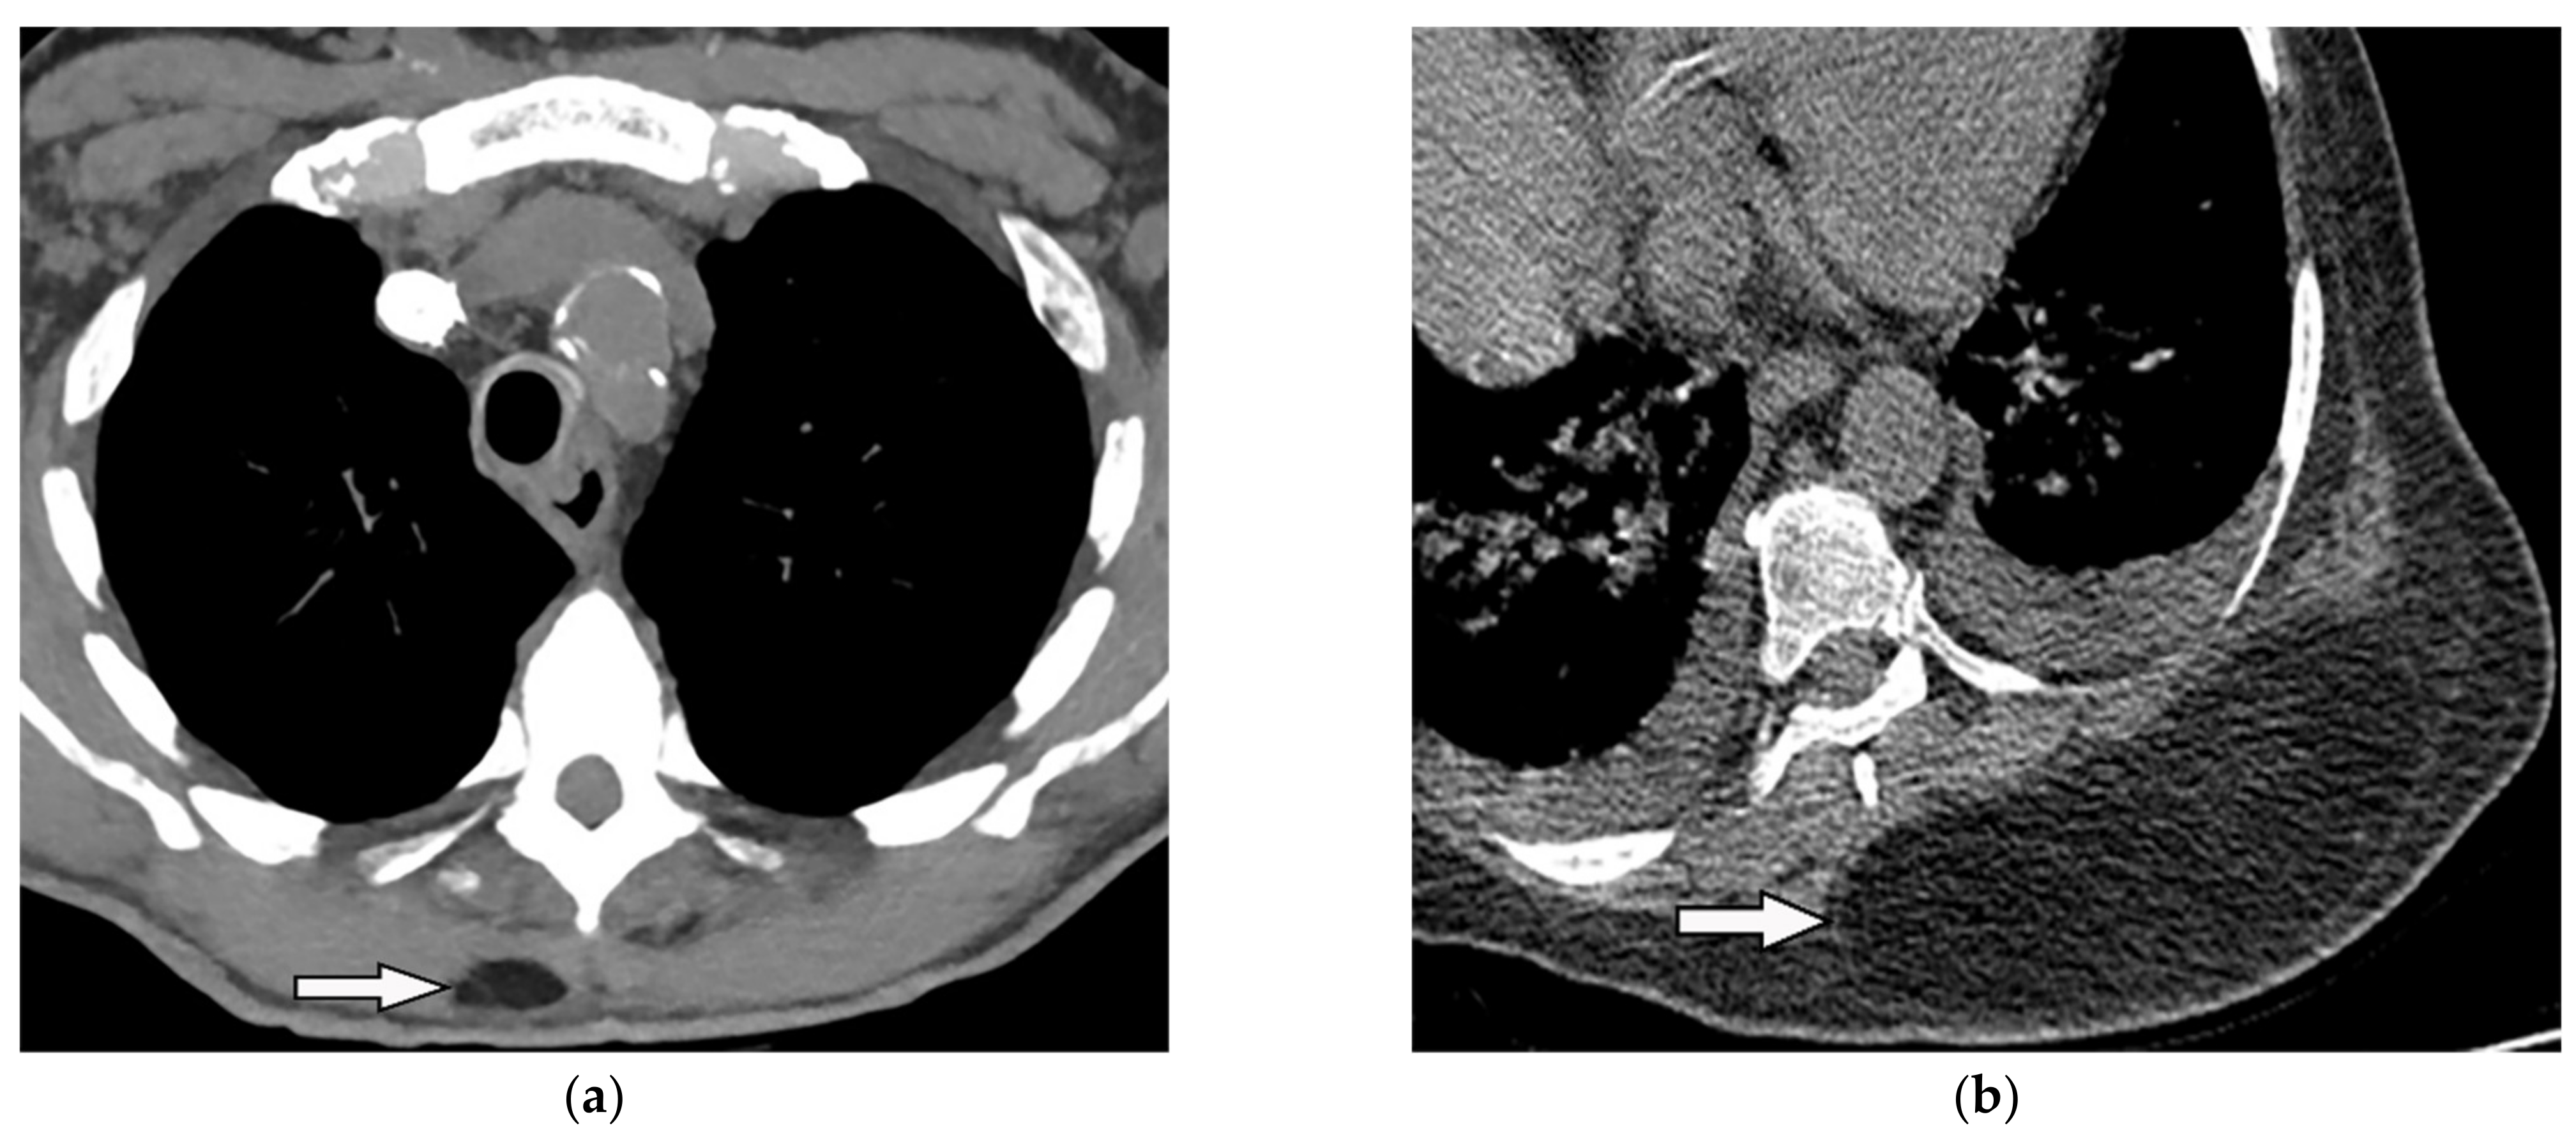

11.1. Empyema Necessitance

| Empyema necessitance | Connection of pleural collection to extrapleural mass, soft tissue inflammation, rib destruction with periosteal reaction, and fluid collection. | T1W: hypointense effusion and fluid collection T2W: hyperintense effusion, increased thickness of extrapleural fat, and chest wall muscles with hyperintense on T2WFS T1WFS + C: pleural and septal enhancement |